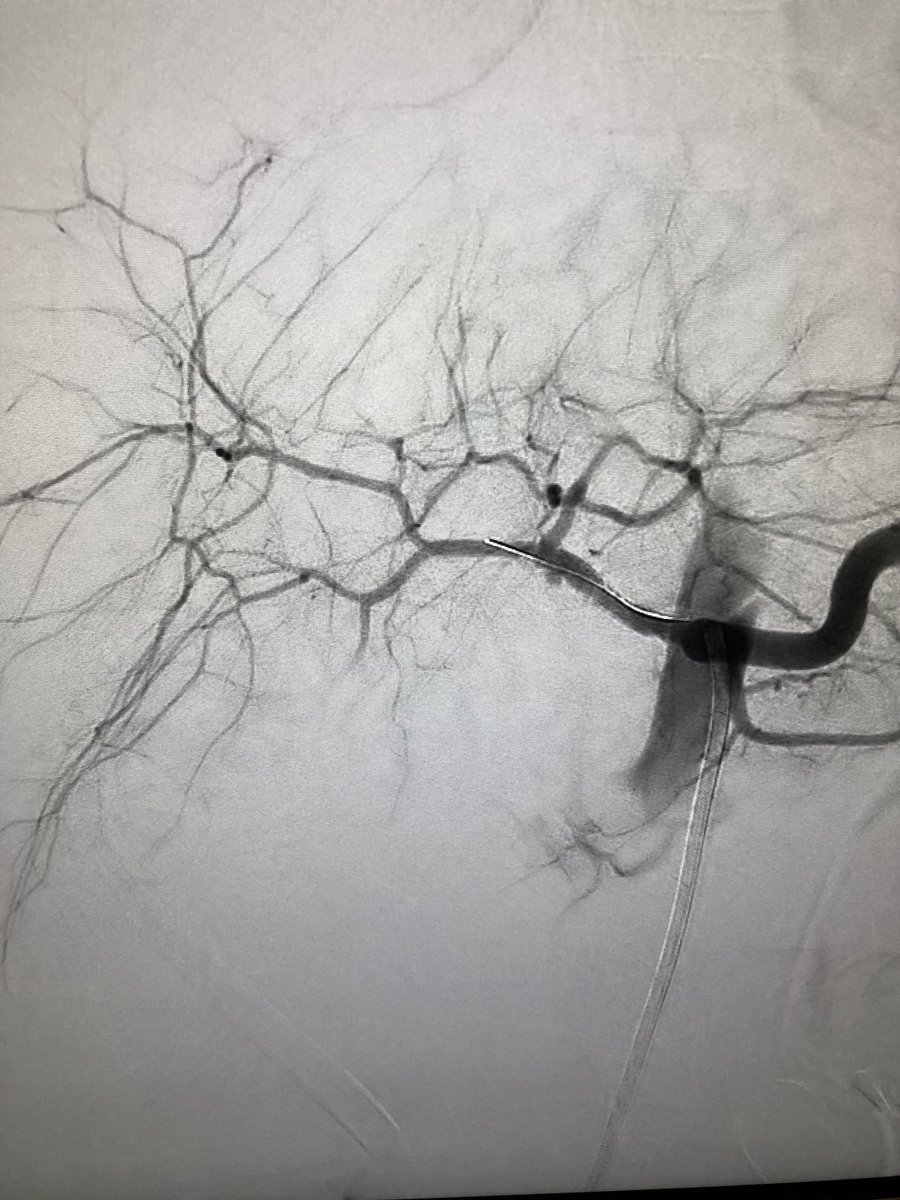

Live

@MountSinaiIR 2.5cm celiac artery aneurysm status post coils with 21#InterlockCoils into the aneurysm and proximal branches with no more flow. Post-embolization SMA run shows collateral filling of celiac branches#IRAD#radrespic.twitter.com/cD6Y7d7Ilx